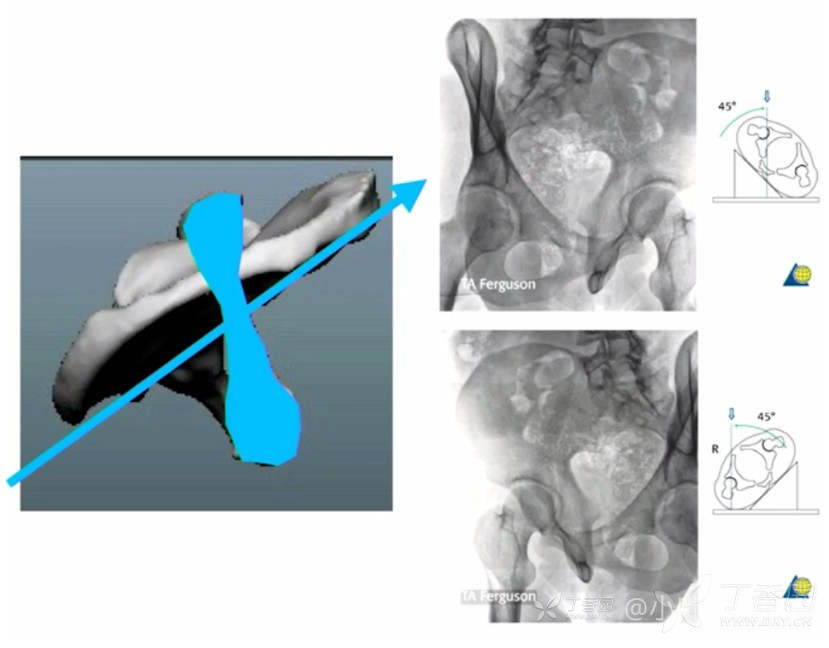

骨盆骨折的Tile分型,骶骨骨折的Denis分型这里都比较简单。髋臼骨折的Letournel-Judet分型看起来就很难,甚至给了你CT的三维机构,一时也看不出来,有没有这种感觉,分型太难没那么简单,其实我觉你还是没有理解其精髓。一但认识了精髓就会在不到1分钟判断出骨折类型,从而给出合适的治疗方案。对于骨盆最近的三柱理论也热度不小,不过万变不离其中,只是在前柱、后柱之上多一个不长见骨折的坐骨支撑柱而已。上图

什么?给了加了股骨头的三维重建还是看不懂?那么接下来是干货。先记住几个重要名词关于X线片的,髂耻线-前柱,髂坐线-后柱,闭孔环-柱,髂骨-前柱,髂骨斜位-后壁,马刺征-双柱。先上图

后壁和马刺征闭孔斜位可以判断出来。看X线片就应该知道骨折分型,当然手术时别的几个位置这里不讲。那么接下来这个表记清楚,这就是归类方法。